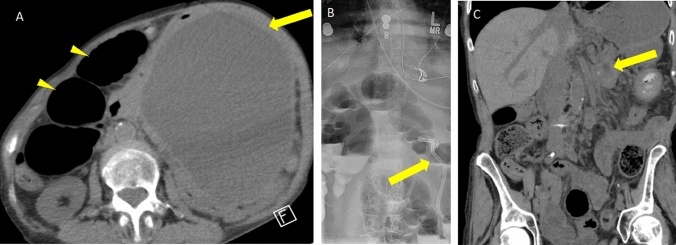

Fig. 14.

Pancreatic pseudocyst causing small bowel obstruction and requiring therapeutic percutaneous drainage. A Axial non-contrast CT in a patient with a large pseudocyst (arrow) in the left abdomen and multiple dilated bowel loops in the right abdomen (arrowheads). B Abdominal radiograph in standing position following placement of percutaneous drain (arrow) into the pseudocyst and persistently dilated bowel loops containing enteric contrast. C Follow-up coronal non-contrast CT 2 months later after drain removal shows a small residual pseudocyst (arrow) and resolved bowel obstruction

Fig. 15.

Infected necrotizing pancreatitis requiring a combination of endoscopic and percutaneous drainage. A Coronal IV contrast-enhanced CT showing large peripancreatic and pancreatic WON containing gas (arrowheads) and an endoscopically placed cystogastrostomy (arrow). B Axial CT during CT-guided drain placement via a left retroperitoneal approach with catheter in appropriate position within the collection (arrow). This approach was chosen to provide a portal for future surgical videoscopic assisted retroperitoneal debridement; however, the patient recovered without the need for surgery